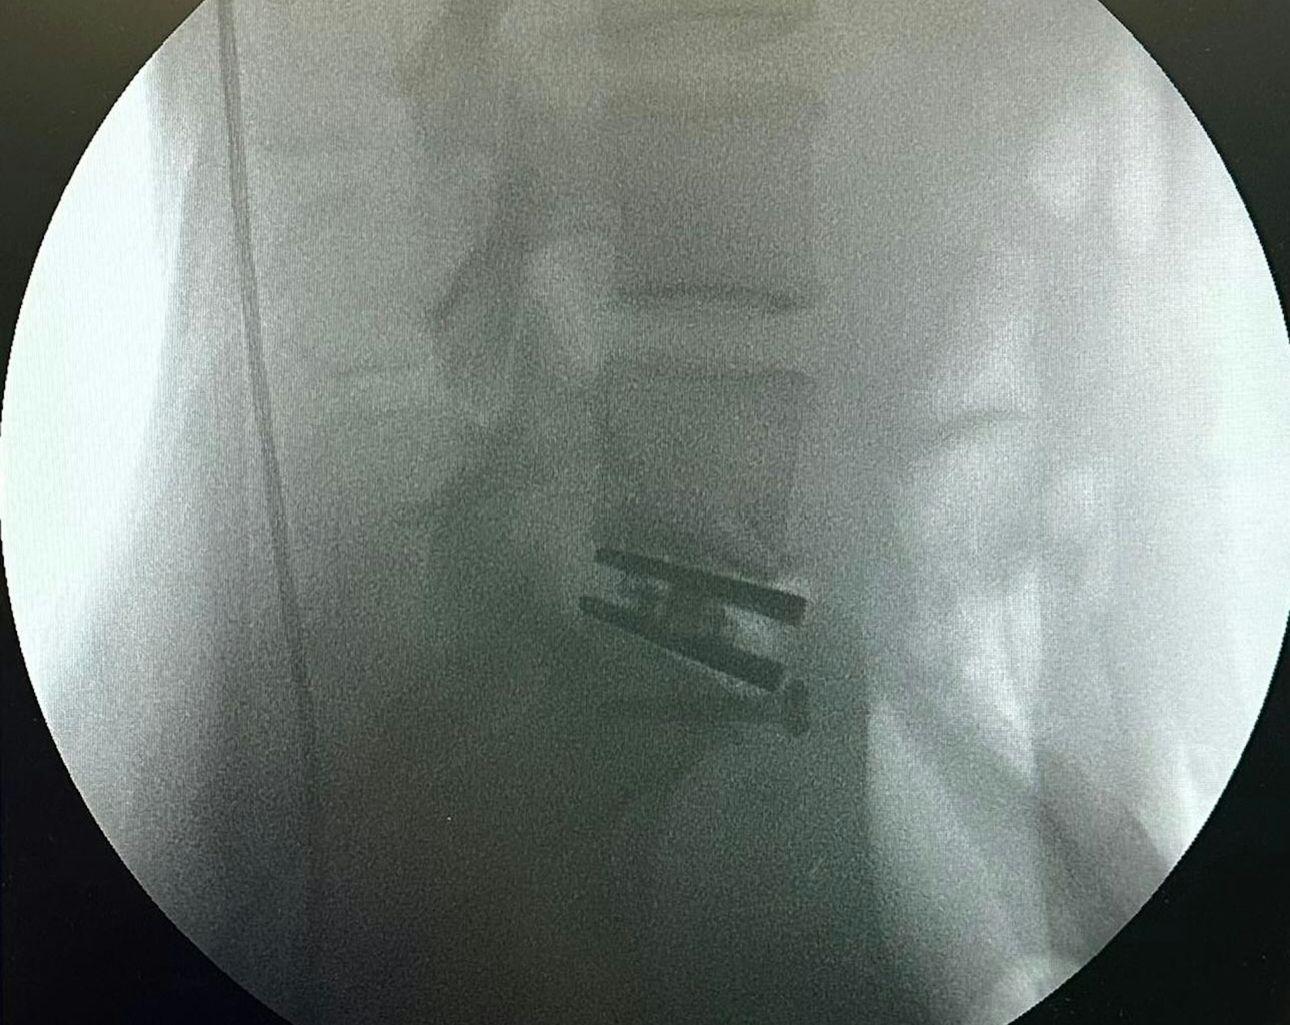

現年50歲的徐濠縈,在IG上載了數張X光片,可以見到片中腰椎接近盆骨的位置有東西矯正脊椎,她亦寫:「I have been suffering from back pain for many years due to a slipped disc issue in my lumbar spine.」透露腰椎間盤突出問題多年,一直飽受腰痛煎熬,嚴重影響了日常生活,熱愛運動的徐濠縈也被迫暫停,即使是打噴嚏的小動作,也會引起劇烈的疼痛,尤其這兩年過得特別難捱。事實上,徐濠縈於2022年已動過一次手術,可惜沒有好轉,她在醫生的建議下決定再次接受椎間盤手術,希望透過這次手術有所改善,她在自言這可能是她人生中繼20年前生下女兒後,最重要的一次手術。目前,徐濠縈已完成手術,正在家中休養。